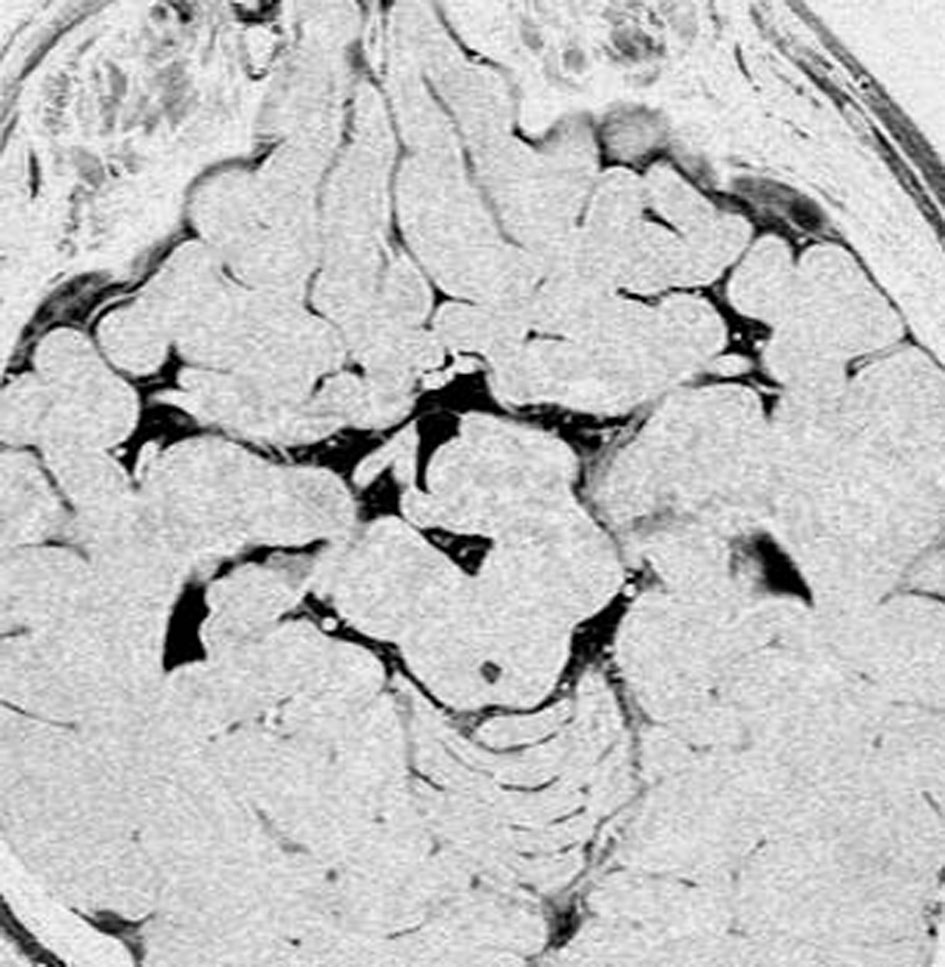

2歳でgelastic seizureを発症,6歳で思春期早発となりました

左視床下部に限局して柄を有するものです,左視索と乳頭体との境界はありません

おそらく左視床下部の機能低下と難治性の発作が原因で,左大脳半球の萎縮(あるいは発達不良)が認められます

予後がかなり不良だと判断して,2004年に摘出術をしました

術後のMRIです,pterional approach でしか摘出できない腫瘍でした

高い位置がとどかず少し取り残しました

gelastic seizureは減荷されましたが残り,術後に視野欠損を後遺しました

2019年時点でもこのよう過誤腫を治療することは困難です